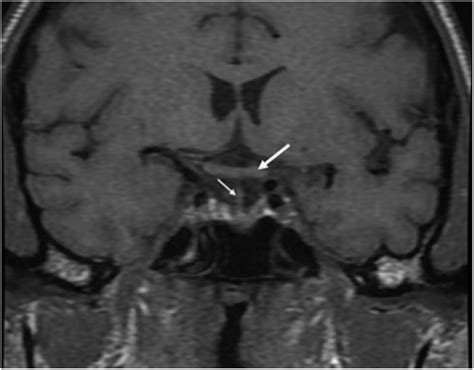

To understand this condition, we must first look at the sella turcica—a bony, saddle-shaped depression at the base of the skull that houses and protects the pituitary gland. In a typical anatomy, the sella is filled primarily by the pituitary gland itself. However, in individuals with an Empty Sella Syndrome (ESS), the sella appears "empty" on imaging results like an MRI or CT scan because it has become filled with cerebrospinal fluid (CSF).

When the condition is classified as a Partial Empty Sella, it means that the sella is only partially filled with CSF, while a significant portion of the pituitary gland remains in its expected position. This can occur due to a defect in the diaphragm sellae—the fold of dura mater that usually acts as a barrier between the brain and the pituitary gland. If this seal is weak, the increased pressure of the CSF can push into the sella, flattening the gland against the bony walls.

If a doctor suspects you have a Partial Empty Sella, they will likely start with an MRI scan, as it provides the most detailed look at the brain structure. Once the imaging confirms the finding, the focus shifts from the "empty" space to the functionality of the gland. A comprehensive evaluation usually involves: